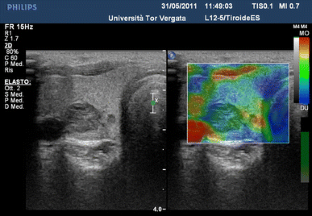

The aim of this study was to determine the accuracy of elastosonography in the differential diagnosis of thyroid nodules using a qualitative [evaluation of the stiffness score (SS)] and quantitative assessment [evaluation of the strain ratio (SR)].

Forty-four nodules were malignant (TIR ≥ 3) and 324 benign on cytological analysis. Considering a cut-off of SS > 2, we had 91 % sensitivity, 68 % specificity, 27 % PPV and 98 % NPV. Considering a cut-off of SR ≥ 3.28, we had 81.8 % sensitivity, 82.7 % specificity, 39.1 % PPV and 97.1 % NPV.

The SR calculation did not provide additional data to the SS, which remains the elastosonography benchmark. It will be necessary to validate these preliminary data by larger prospective randomised trials.